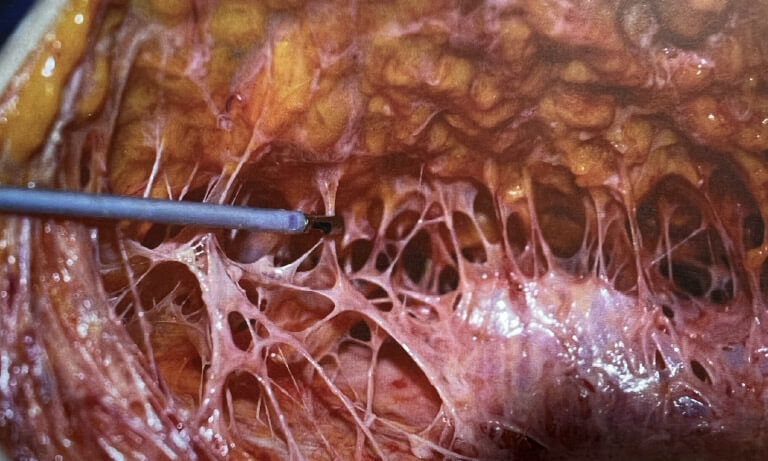

什麼是 FSN 想像一下,皮膚底下有一張細緻的網子,把皮膚和下面的組織牢牢連接著,這張網子就是「纖維隔膜」。

抽脂為什麼會傷到它? 如果抽脂管用得太粗,或是手法太粗魯,就會把這張網子給「撕裂」掉。一旦網子破了,皮膚就失去支撐,開始鬆垮、下垂,甚至出現「皮肉分離」的感覺,表面也容易變得凹凸不平。

皮下的纖維支撐網是讓維持彈性與立體的關鍵

纖維隔膜(FSN)

這很重要!它就像一張細密的網子,把脂肪細胞分隔開,同時把皮膚「固定」在下面的筋膜上。這張網子決定了皮膚的平整度和緊實度

如果FSN斷裂或鬆弛,皮膚就會像被拉開的麻糬,鬆鬆垮垮。因此,若抽脂時破壞了 FSN,皮膚表面就會出現凹凸不平的問題。

Fibro-Septal Network (FSN)